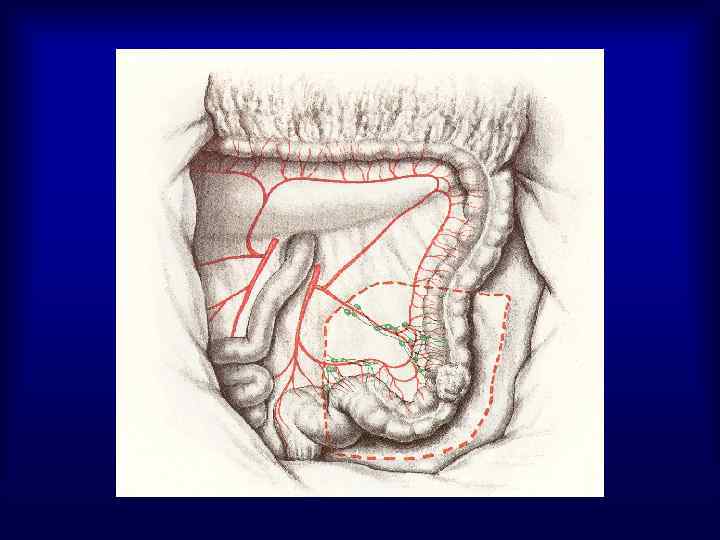

Виды операций при раке прямой кишки 1. Брюшно-промежностная экстирпация прямой кишки (25%) 2. Чрезбрюшная (передняя) резекция прямой кишки (50%) 3. Брюшно-анальная резекция прямой кишки (25%) 4. Операция Hartmann (5%) 5. Экономные операции – при размерах опухоли 1 -4 см, расположенных на расстоянии 3 -10 см от заднего прохода (трансанальное иссечение скальпелем, электроножом, лазером, криодеструкция, эндоскопическая коагуляция)

Хирургическое лечение рака прямой кишки 1. 2. 3. 4. Чрезбрюшная резекция прямой кишки выполняется при локализации опухоли не ниже 8 см от анального кольца Брюшно-анальная резекция прямой кишки с демукозацией слизистой анального канала и формированием колоанального анастомоза могут осуществляться у больных с локализацией опухоли на расстоянии 6 см и выше от аноректальной линии Операция Hartmann выполняется у пациентов пожилого и старческого возраста, с сопутствующей патологией, при наличии непроходимости, распадающейся опухоли, отдаленных метастазов с локализацией процесса не ниже 8 см от ануса Брюшно-промежностная экстирпация ПК выполняется при локализации опухоли в анальном канале, при нижнеампулярных раках, а также при возникновении интраоперационных осложнений